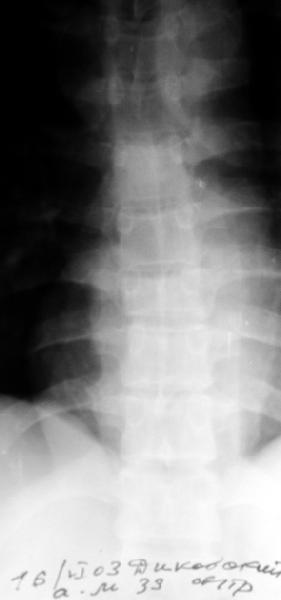

Перелом IX грудного позвонка

Мужчина 39 лет, перевернулся в машине 12 июня. Клинически неврологии нет. Нужна ли репозиция и оперативная фиксация этого повреждения? Если нет, то как вести? Спасибо заранее.Алексей Рунков, УНИИТО

Agreed, except that loss of posterior vertebral body height on the lateral radiograph suggests middle column involvement as well, and therefore a diagnosis of burst fracture. This is confirmed on the AP by (albeit subtle) widening of the pedicles at the level of injury. In keeping with this diagnosis, the lateral also suggests retropulsion of fracture fragments into the canal. I concur that unless there is associated facet subluxation or interspinous widening on CT (possible, but unlikely given the well-maintained alignment and given that on the AP radiograph the spinous processes seem reasonably equidistant) this is a stable burst fracture that I would treat with a TLSO for 3 months.

The lack of any neurological sysmptoms suggests that this man has a stable fracture despite losing 50% of his vertebral height. Initial management would be analgesia and bedrest until comfortable, and then the application of a hyperextension brace to prevent kyphosis. With this fitted he can be mobilised and can sit, and provided home situation is reasonable, should be able to go home after only a few days, with the proviso that he is still flat for part of the day. I would expect him to wear the brace for at least 2 months.